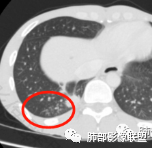

看肺窗病灶边界很模糊,以及胸膜下局限性积液,支持炎性

但是远端部分很散,边界清楚,应该是周围伴有炎症

4.远端有树丫,提示炎症一定存在的

边缘:肿块边缘无GGO是同高分化腺癌的主要鉴别点,多可见浅大分叶,当发现有内凹切迹时提示压迫增殖型肺癌膨胀发育,切迹处可见阻挡肿瘤发育的支气管血管,低分化鳞癌边缘凹凸更加明显,而无分叶主要见于高分化鳞癌,浸润收缩型鳞癌,边缘不整,棘状缘,出现支气管血管集束改变,类似分化型腺癌。中央型肺癌可见背离肺门侧肿块边缘因阻塞性炎症而显示不清,又称为彗星尾征。

胸膜浸润:周围型鳞癌有胸膜浸润者,术后生存率多为1年,其胸膜浸润多为台状肥厚(板状肥厚),其范围往往超过病灶直径的1/2,累及壁层胸膜形成胸膜桥,即胸膜栽赃,偶有胸膜凹陷,与腺癌相比,其胸水发生率相对较低。

一般来讲,鳞癌收缩力弱,胸膜凹陷及牵拉少见,空洞坏死多见,而此例出现了“胸膜凹陷”,如下图:

这种特点在鳞癌比较多见  周围型鳞癌经常这个形态,外周有类似喇叭样收缩形态,考虑周围型鳞癌引起局部肺不张,所以有远侧内收而缺乏侧面收缩力。

回头看发现肿块近肺门侧边缘清楚,而远肺门侧边缘模糊,多考虑肿块阻塞支气管引起的阻塞性炎症,支持周围性鳞癌引起局部肺不张观点,两者形态相似,易与胸膜凹陷征混淆,小编认为,因肺不张为实变的肺组织,而胸膜凹陷为脏层胸膜受肿块牵拉凹陷形成的含液腔隙,故鳞癌形成的“胸膜凹陷”其密度较高,多为实性密度,而真正的胸膜凹陷征其内部密度较低,多为液体密度。